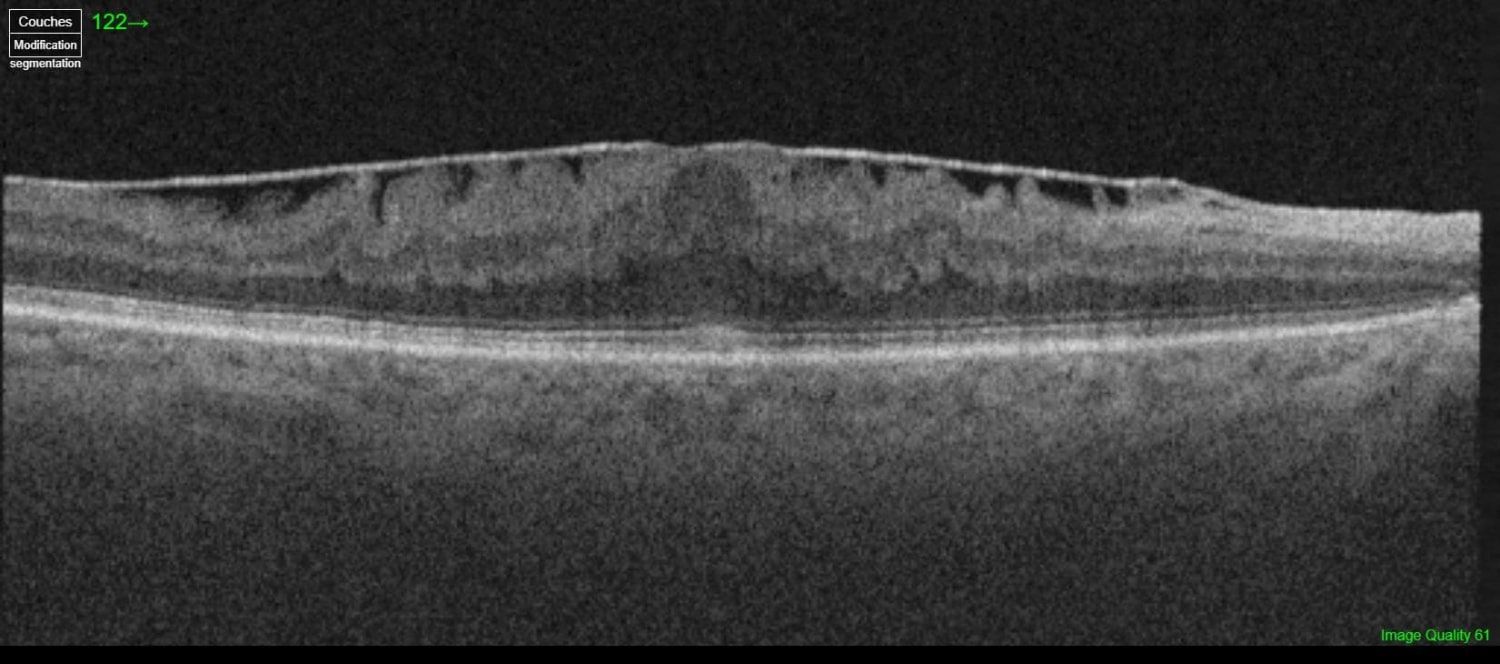

Le diagnostic d’une membrane épirétinienne se fait grâce à l’examen de la macula au fond d’œil mais surtout grâce à l’OCT. Il est absolument essentiel. Il permet d‘évaluer l’importance de la membrane au fond d’œil et également l’importance de la déformation de la macula.

On peut schématiser une membrane épirétinienne comme une fine couche de cellophane qui serait déposée sur la rétine, avec le temps celle-ci peut s’épaissir, se contracter et ainsi déformer la macula.